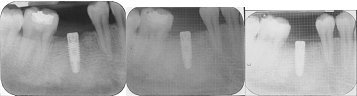

IOPA Immediately, after 1st and 3rd month post operatively after Implant Insertion